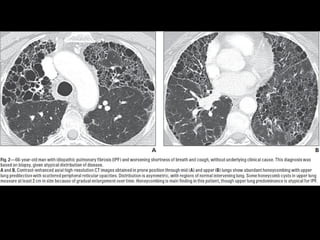

Fibrosis pulmonar idiopática •Causa desconocida • Es la más común de IIP 50-60% • Patrón histológico y TC: UIP exposición a drogas y polvo, neumonitis hipersensibilidad crónicas, colágeno y asbestosis D: excluir causas

FPI • >50 ,h • Síntomas gradual, disnea, tos seca • No responde a corticoides • Pronóstico pobre, 2-4 SV • Muerte: falla respiratoria, cor pulmonare • Secundario: mejor pronóstico

UIP histología • Combinaciónheterogénea de inflamación intersticial, fibrosis y panalización con áreas normales • *biopsia puede desestimarse

UIP TC • Fibrosiscon áreas normales. • Disminución de volumen pulmonar • Opacidades reticulares • Vidrio esmerilado • Predominio en regiones basales y subpleurales • Distorsión arquitectónica con bronquiectasias por tracción secundaria a fibrosis. • Panal de abejas (2-20mm) • Linfoadenopatías mediastínicas pequeñas.